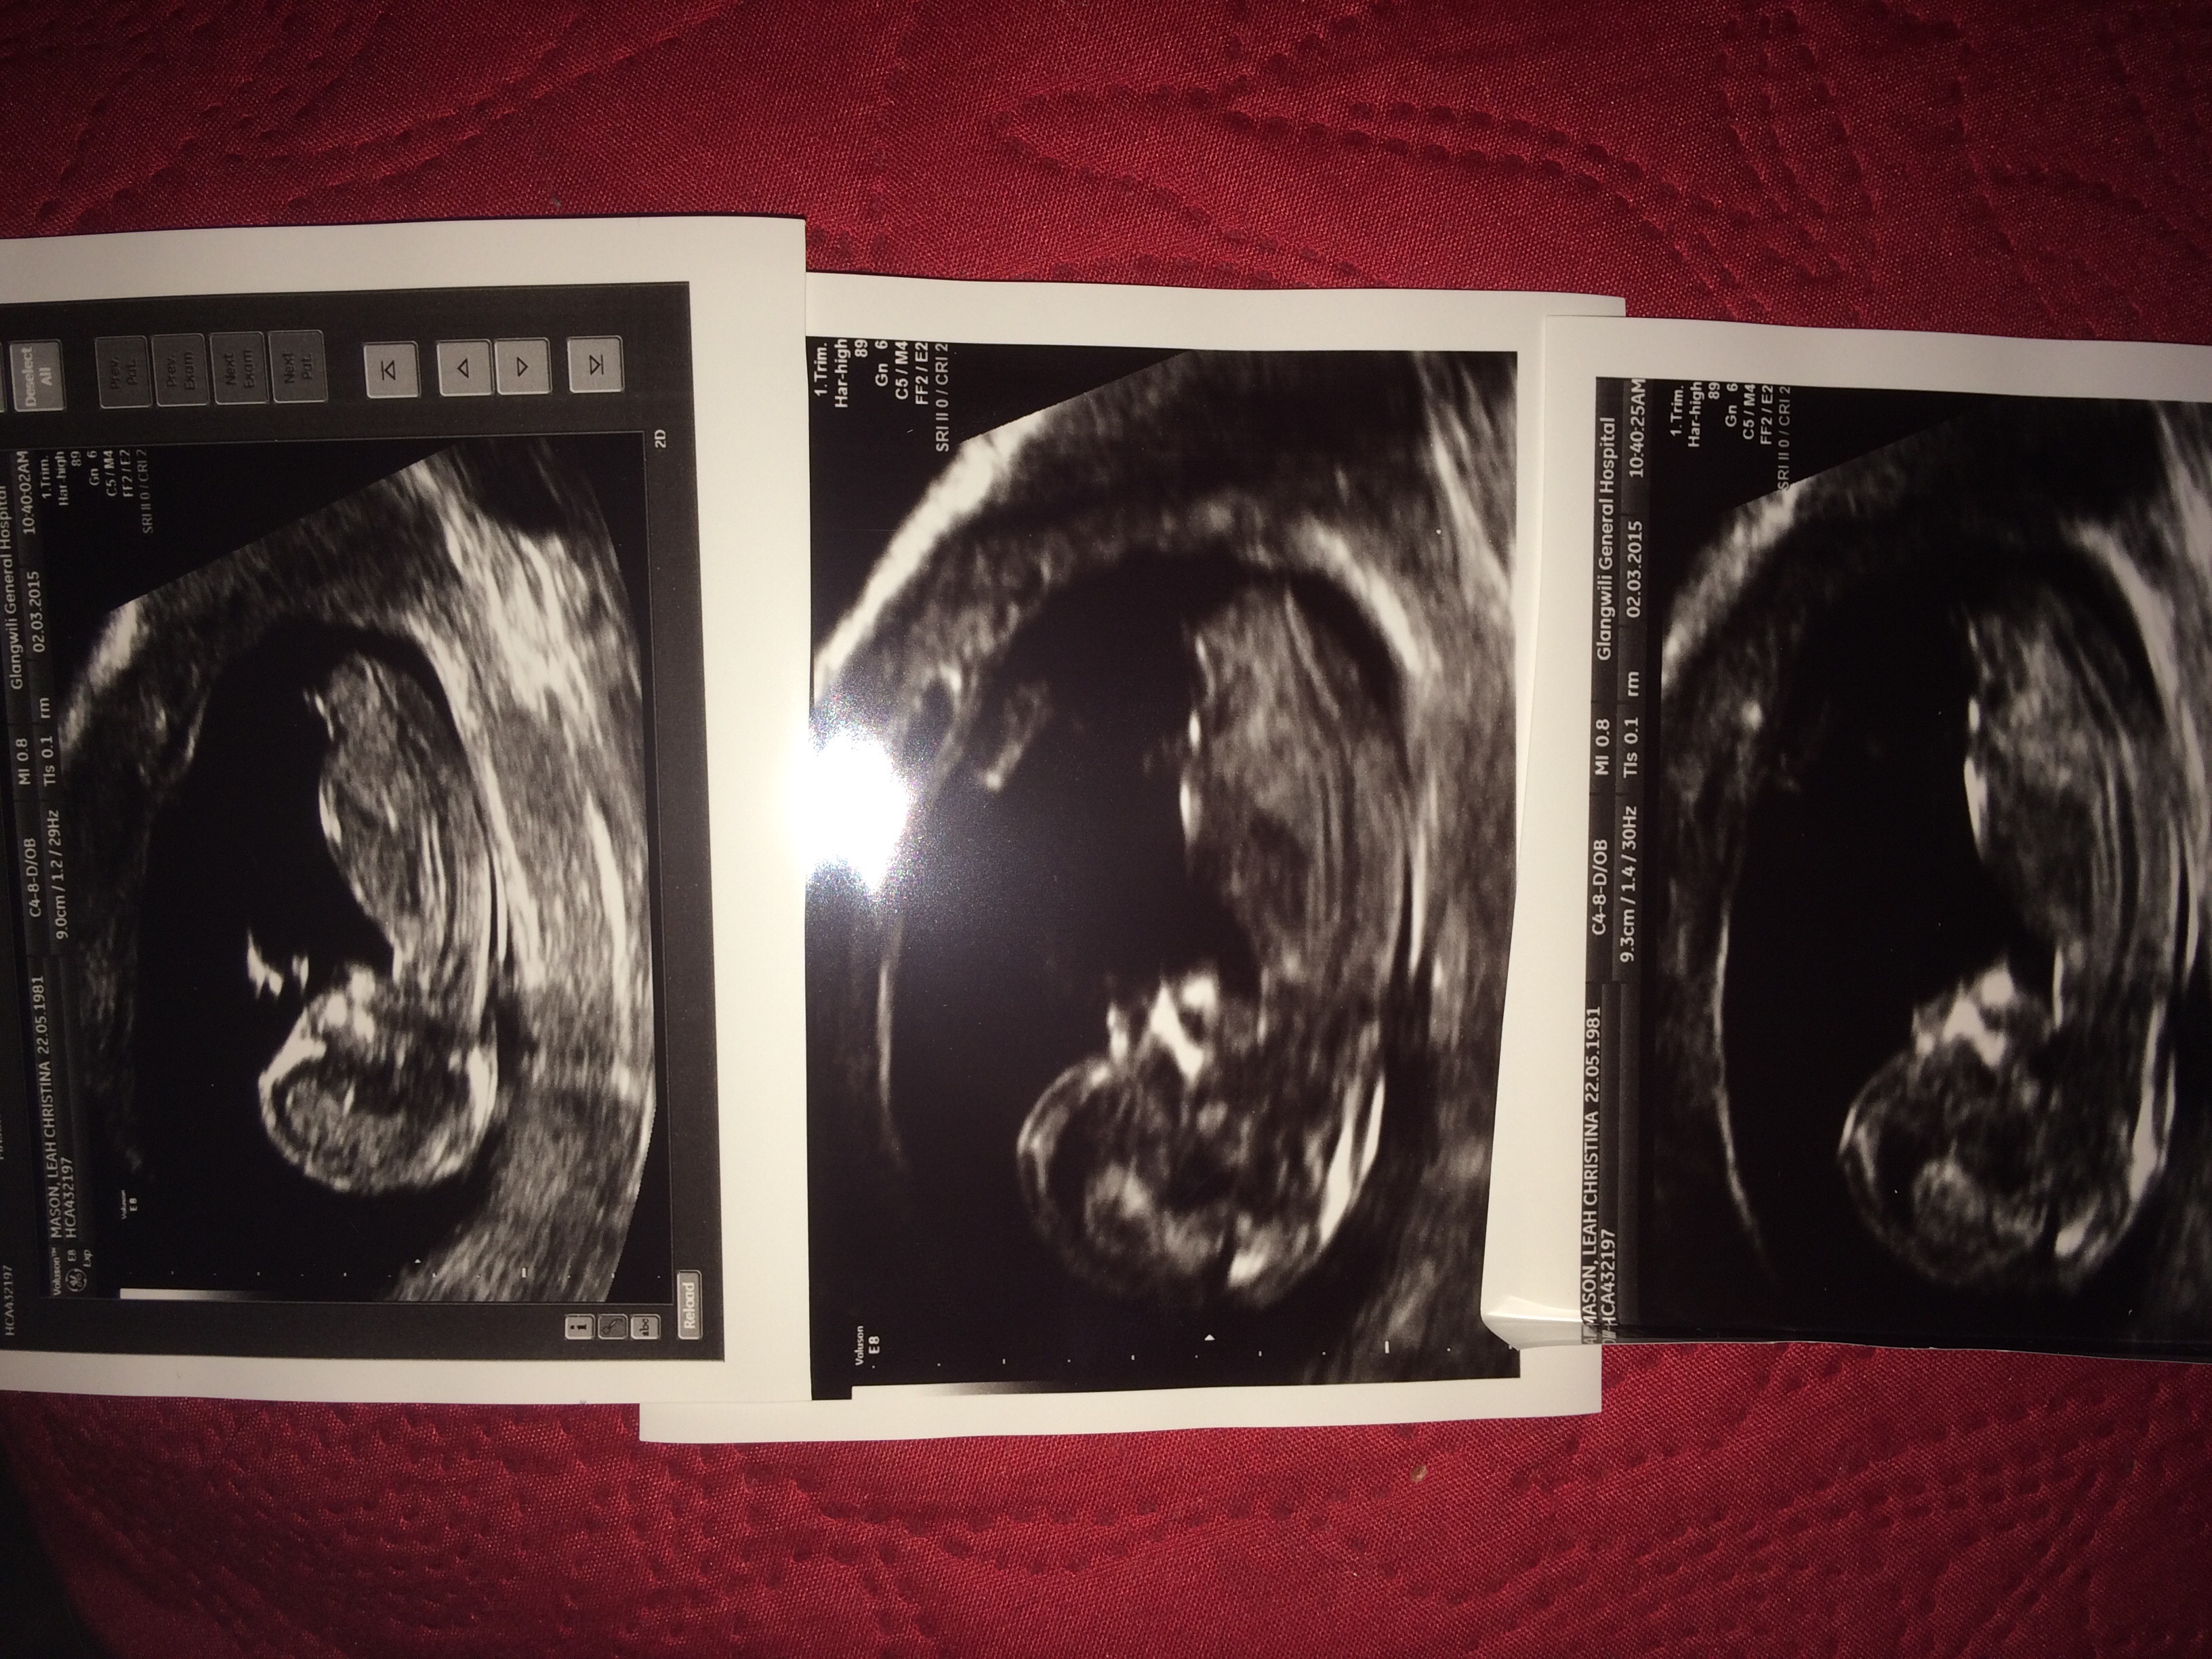

Guesses please! XxAttachment 24208Attachment 24209

12+3 is early, but to me it looks girly. I've seen lots of stacked nubs that have ended up being girls so to me that's not what indicates gender, I look more at the angle of the nub, which in your pics is very parallel to the spine which makes me say girl.

This is a tricky one. On the first two it's short and stacked (boy) but on the last picture it's longer and parallell to the spine and forked (girl).

I see a girl. The bladder is right behind the nub and the nub looks long and flat. Unsure whether that’s stacking in the first 2 pics but I’m guessing girl.